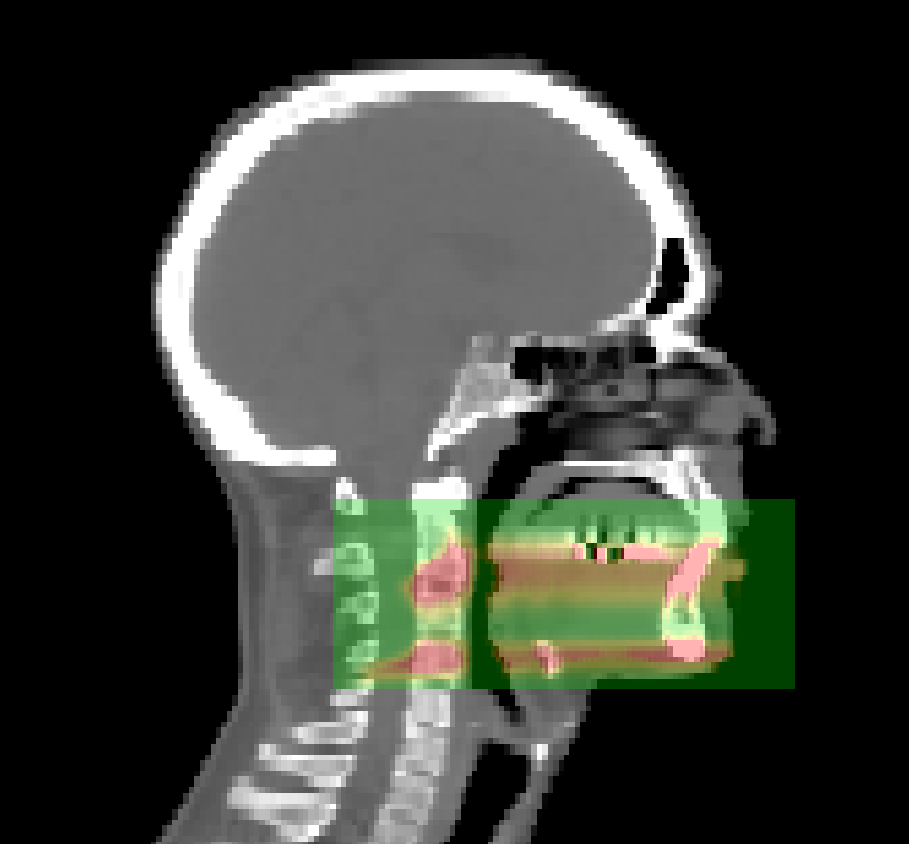

Two test cases are presented. The purpose of Test case 1 is to verify that the transition to voxels has been done correctly. The phantom proposed by Parodi et al. (2005) and used by El Kanawati et al. (2015) is converted into a voxelized representation, see figure 3. In Test case 2 (fig. 4), a clinical head and neck image with corresponding proton therapy treatment plan is examined and is intended as a demonstration of the possibilities of the vpgTLE method. Precise beam properties may be found in table 1. Compared to El Kanawati et al. (2015), the number of analog primaries used for the reference are increased from to . This is required in order to obtain a sufficiently noiseless figure for the spatial projection along the beam axis. For the vpgTLE simulations, four simulations are executed with , , and primaries respectively. Next, we define certain windows of interest. Knowing that most PG detectors do not measure outside the 1-8 MeV energy range (Testa et al., 2013), or even narrower (Smeets et al., 2012), we limit our analysis to this energy window. In addition, PG yield outside the spatial region that represents 90% of the total yield in the reference simulation is discarded. For all analyses these two cuts are applied.

The current implementation of vpgTLE stores each bin as a double (64 bit) in memory, and converts to float (32 bit) when writing to disk. The memory consumption is therefore linked to the number of PG bins, image and voxel size. By default the vpgTLE actor will copy the size and voxel size of the image it is attached to. As described before, for clinical CT images this will result in on-disk images of tens of GBs, and twice that in memory usage during the simulation. In this paper, we therefore shrank the PGyd volume to a region that envelops the PG production sites with some margin (see figure 10). This resulted in an on-disk image size of about 104 MB. With 1 mm voxels, the image size increases eight-fold to 833 MB (double at runtime: 1666 MB). A PGyd with the size of the CT data used in Test case 2 with 1 mm voxels would blow up to 120 GB on disk, 240 GB in memory at runtime.

Test case 2: PGyd output region